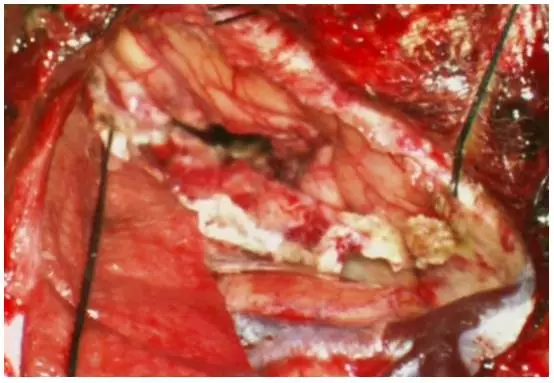

图11. 用缝线牵开大脑镰的硬膜瓣(小图),向对侧大脑半球(患侧)方向牵开,以增加到达同侧房部(健侧)的操作角度(上图)。相应的术中图片如下图所示,可暴露左侧楔前叶(吸引器尖端)。棉片保护健侧脑组织,以避免牵拉损伤。未使用固定牵开器。

图12. 图示为切除左侧巨大房部脑膜瘤后,楔前叶皮质切开的范围。一条牵开大脑镰硬膜瓣的缝线已经去除,以便更加清楚的展示手术通道。